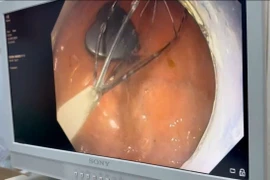

Các bác sĩ Bệnh viện Hữu nghị Việt Nam - Cuba Đồng Hới đã phối kết hợp, thực hiện thành công nội soi phế quản cấp cứu lấy dị vật dưới gây mê cho bệnh nhân 9 tuổi nuốt phải xương cá khi ăn cháo.

Dị vật đường tiêu hoá nếu không được phát hiện sớm và điều trị sẽ gây ra các nguy cơ chảy máu, thủng ruột, tắc ruột, áp xe ổ bụng, nghiêm trọng hơn có thể gây nhiễm khuẩn huyết nguy hiểm đến tính mạng.